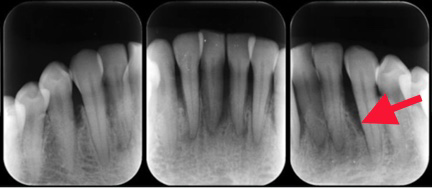

それでは詳細のレントゲンで骨の状態を確認していきましょう。赤の矢印が骨の位置を示しています。

歯石取り(歯周初期治療)後